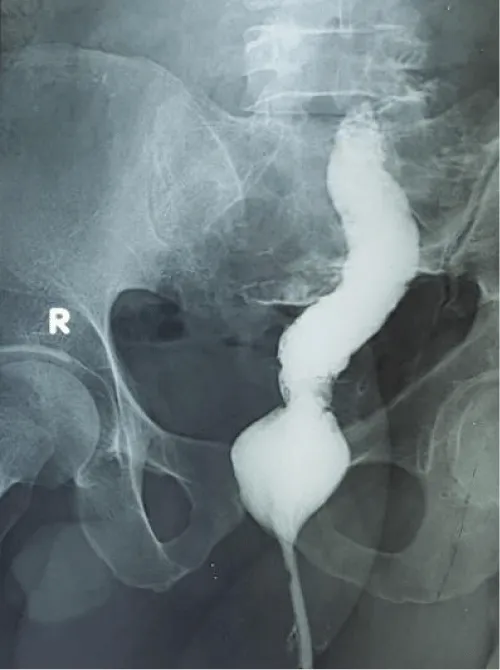

A 45-year-old man presented in the emergency department with a painful and irreducible rectal prolapse. Patient gave a history of recurrent rectal prolapse for 2 years. On examination, he was found in severe pain and discomfort, with a prolapsed rectum that looked swollen, congested with black discoloration of the mucosa (Figure 1). He experienced severe tenderness on the attempt of manual reduction. A decision was taken to perform emergency surgery. He was operated on within 6 hours of admission on the emergency list. Per-operatively, all layers of the prolapsed rectum were found unviable. Complete resection of the rectum and colon was done by Altemeier’s procedure. The rectum was transected 3 cm proximal to the dentate line. The circular stapler could not be used for colo-anal anastomosis as the rectal wall was severely edematous. Anastomosis was done by an interrupted Vicryl suture (Figure 2). The rectum was then pushed back to the pelvis easily (Figure 3). A transabdominal loop sigmoid colostomy was done to ensure uncomplicated healing of the edematous anastomosis. Sigmoid colostomy was closed 3 months after Altemeier’s procedure. The bowel continuity and good patency were confirmed by barium enema before closure of colostomy (Figure 4). Patient made an uneventful recovery after colostomy closure. His defecation was normal. There was no incontinence either. There was no recurrence of prolapse after one year follow up.

Figure 4: Good lumen on Barium enema.

There are two surgical approaches for full-thickness rectal prolapse, which are the abdominal approach and the perineal approach. Our case was an incarcerated full-thickness prolapse of the rectum. Hence abdominal approach was not at all suitable. In this situation perineal approach was the only option. Due to gangrene of the rectum and sigmoid colon, complete resection of the prolapsed bowel and colo-anal anastomosis was necessary. Another name is Altemeier’s operation. Anastomosis of edematous bowel was a concern in our case. Fortunately, the anastomotic line was not ischemic but edematous only. Circular stapler-assisted anastomosis was not feasible for the same reason. A trans-abdominal construction of a sigmoid loop colostomy was needed to protect the hand-sewn anastomosis. A protecting loop ileostomy could also be an alternative. There are some case series of Altemeier’s operation where a loop ileostomy was performed with good results [3,8]. But if elective Altemeier’s operation is done after bowel preparation, a protective stoma is not necessary [9].